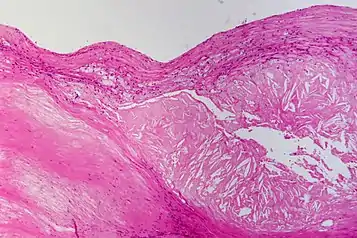

![]() | Mucinous cystadenoma | Micrograph showing Mucinous Cystadenoma of ovary. The cyst wall is lined by tall columnar epithelium and filled with mucin. | Category: Histopathology of mucinous cystadenoma | Mucinous cystadenoma |